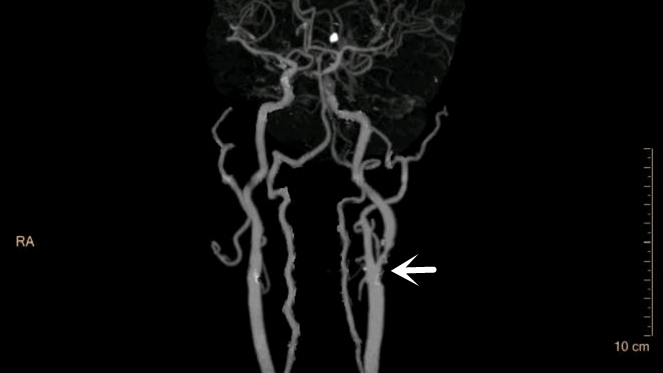

图中所示为颈动脉狭窄

前段时间,芝罘区的王先生因频繁头晕不适到烟台山医院就诊,在做颈动脉增强CT检查时发现左颈内动脉起始部有大的斑块,斑块导致血管管腔严重狭窄,狭窄率已经达到85%!